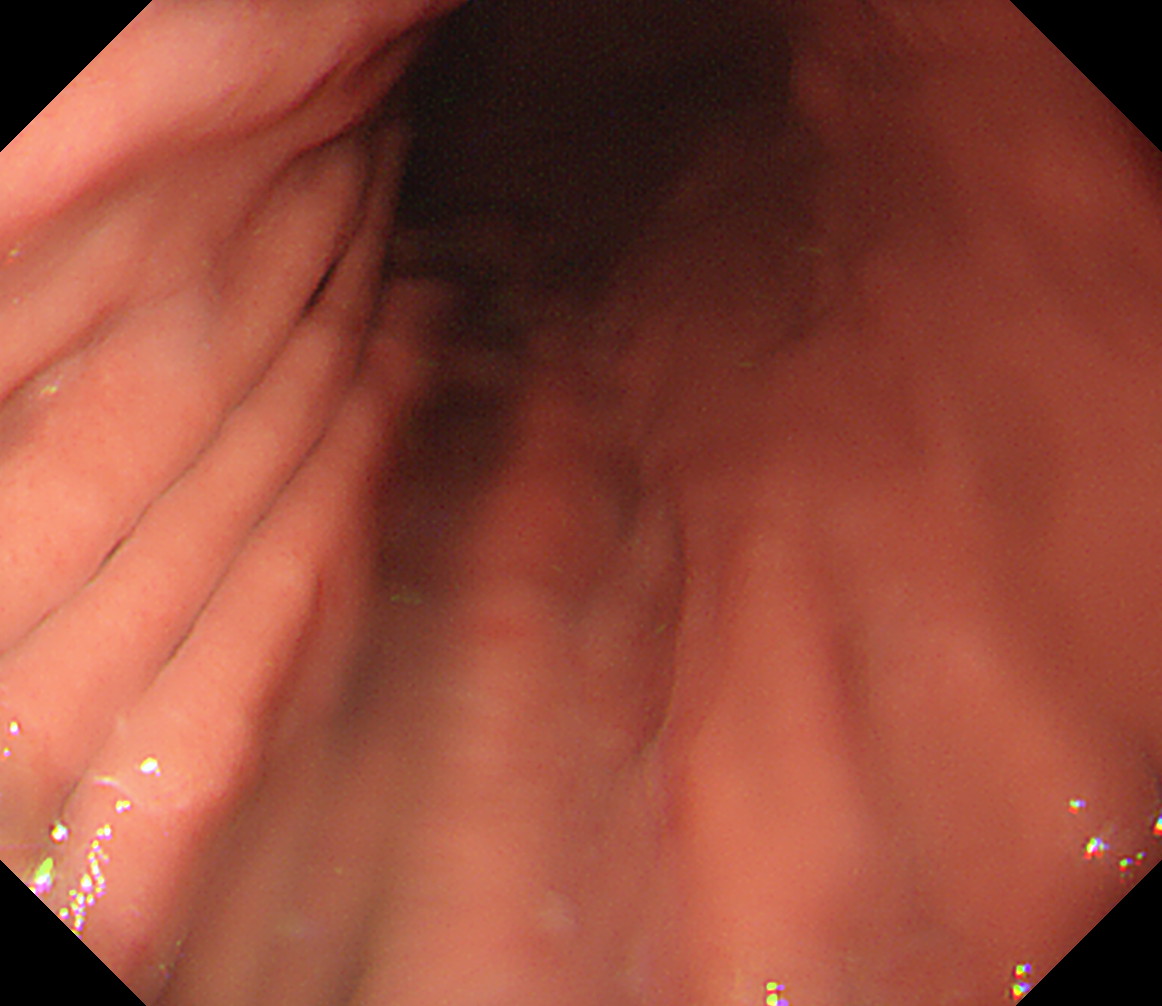

23 胃角部大弯 以下ずっと[見下ろし]でくるくる反時計方向に回しながら引き上げていく

萎縮境界の観察なども行います

胃角部大弯

24 体下部後壁 引き上げて

後壁から反時計回り

接線になり見逃しやすい部位です

体下部後壁